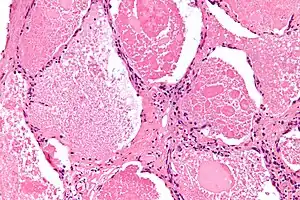

Proteinose alveolar pulmonar (PAP) Proteinose alveolar pulmonar é uma doença rara na qual um líquido rico em proteínas (surfactante) enchem os alvéolos prejudicando as trocas gasosas. Afeta quatro em cada milhão de habitantes, geralmente adultos.

Pode ser diagnosticado por Raio X revelando consolidação pulmonar, por exame histopatológico e em exames físicos pode-se identificar ruídos inspiratórios, baqueteamento digital e cianose periférica e/ou central